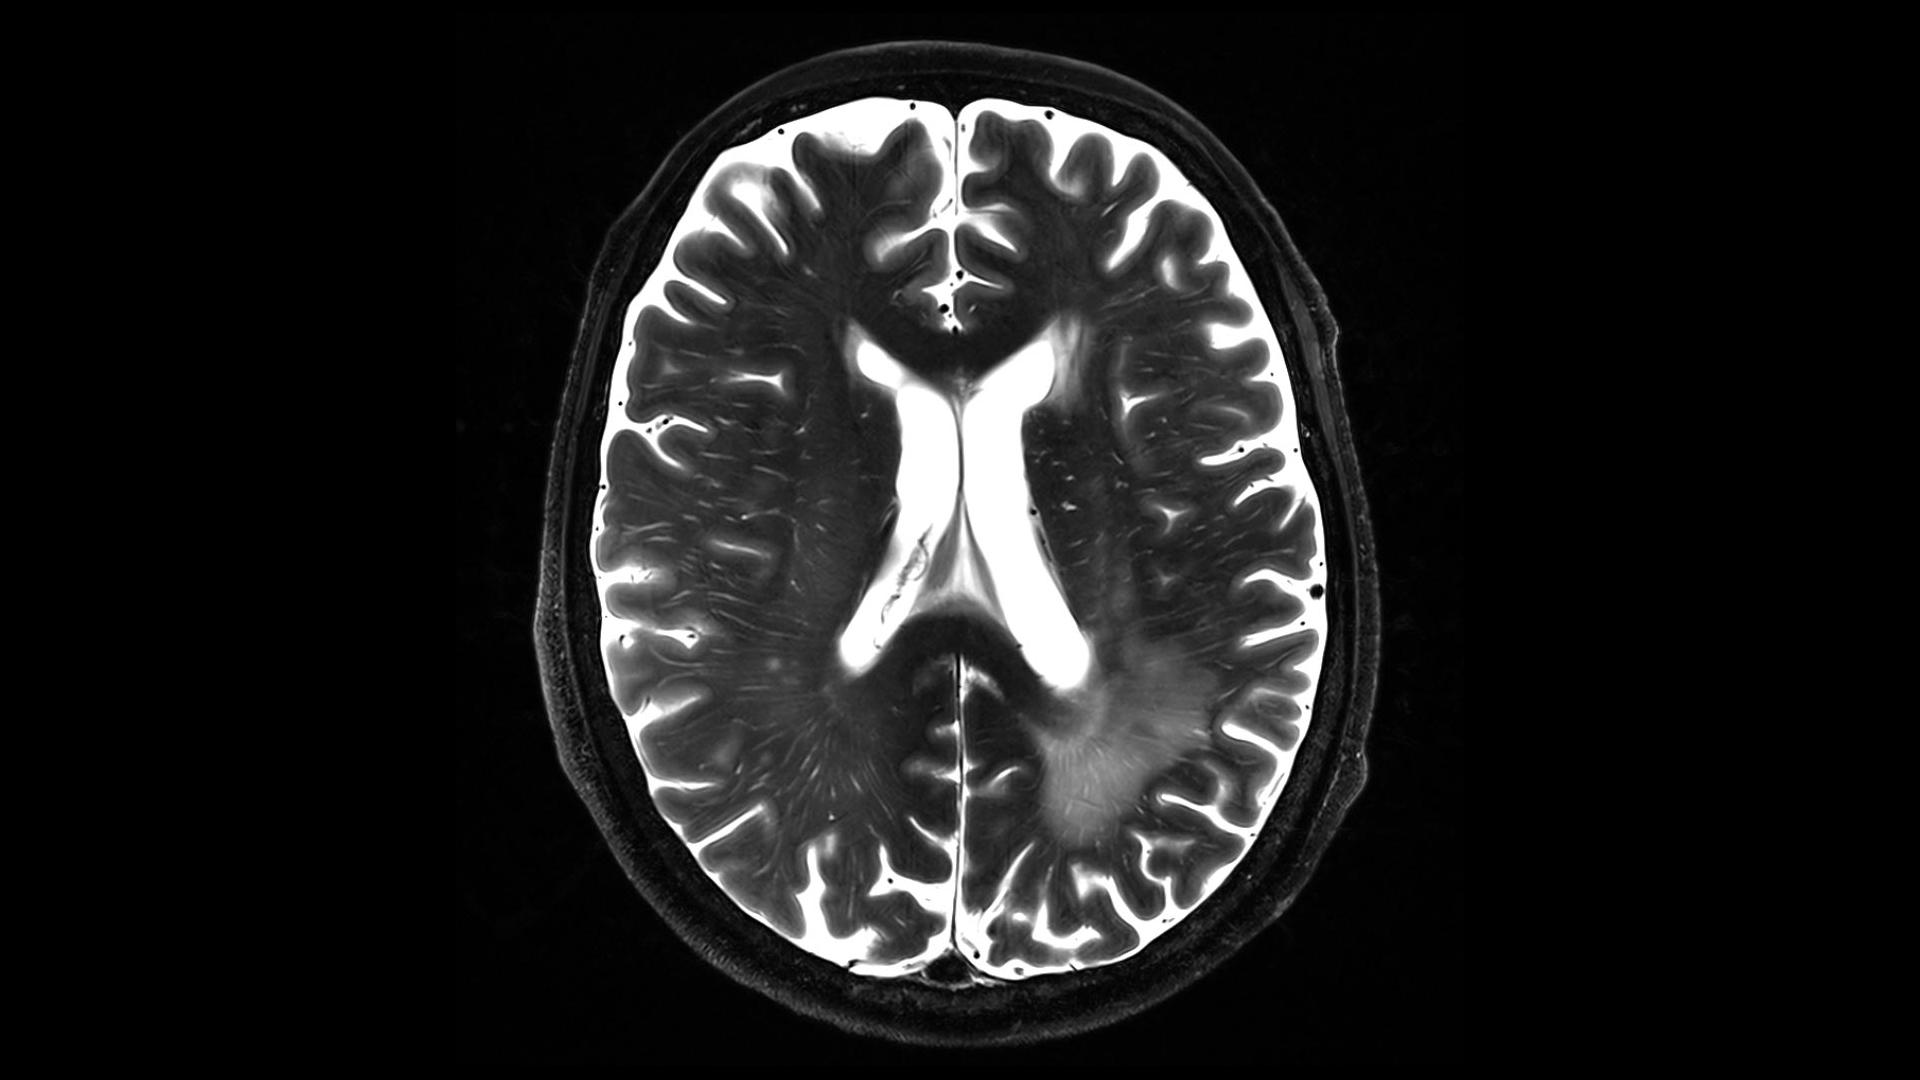

Improved User Interface and AI-Driven Image Reconstruction

The MAGNETOM Terra.X introduces a revamped user interface and software environment, offering an intuitive and streamlined experience for our researchers and clinicians. But that’s not all – the incorporation of advanced image reconstruction techniques based on artificial intelligence (AI) ensures unparalleled image quality. This innovative approach accelerates diagnostics and empowers our teams to explore new frontiers in medical imaging research.

Enhanced Gradient Strength for Unprecedented Precision

With a remarkable gradient strength of 130 mT/m and a slew rate of 250 T/m/s, the MAGNETOM Terra.X takes imaging precision to unprecedented levels compared to conventional systems equipped with 80 mT/m gradients. This enhanced gradient strength facilitates faster and more detailed imaging, allowing us to push the boundaries of what is possible in research and clinical diagnostics. A huge boost for functional, diffusion and structural MRI capabilities.